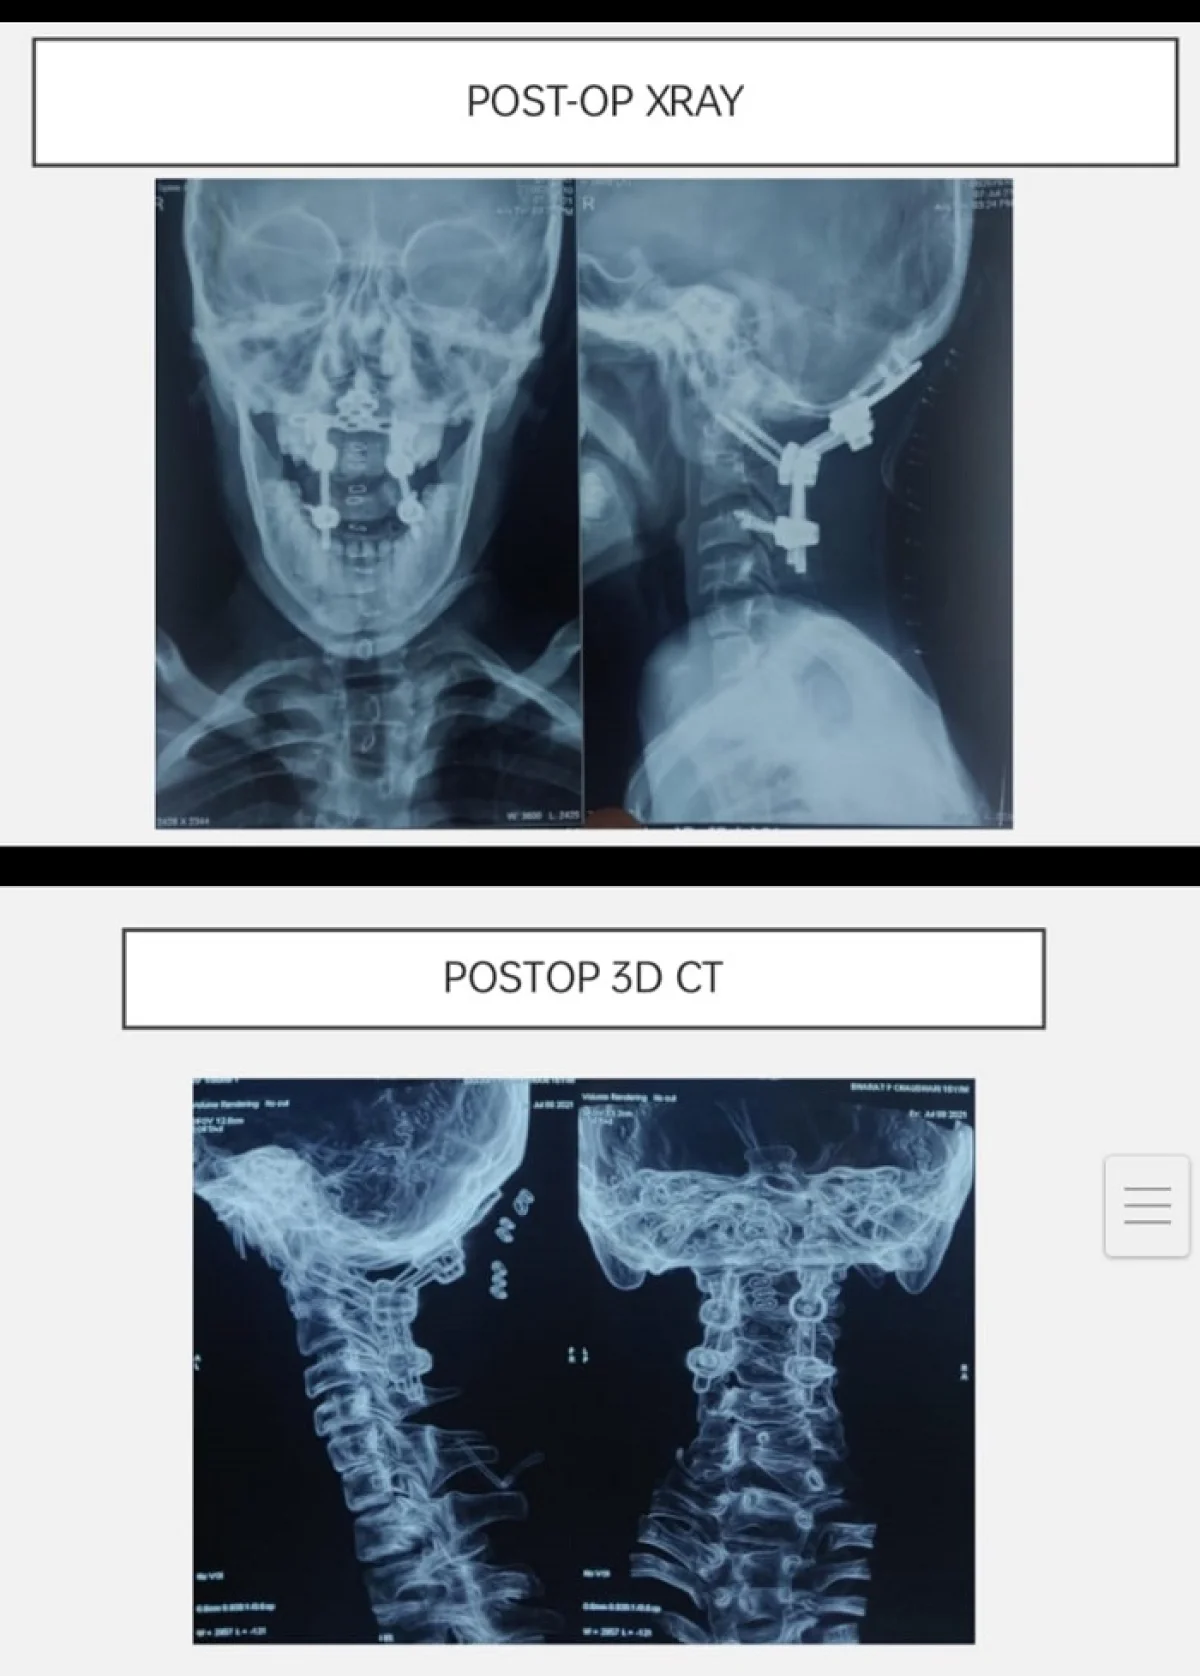

આ રીપોર્ટસના આધારે ભરતના ગરદનનો પહેલો અને બીજા મણકો ખસી ગયેલ હોવાનું જણાઇ આવ્યું. જેને તબીબી ભાષામાં “એટલાન્ટો એક્સીઅલ ડીસલોકેશન” કહેવામાં આવે છે. આ પ્રકારની ઇજાની સર્જરી ખરેખર ખૂબ જ જટીલ હોય છે. કારણ કે આવા પ્રકારની સર્જરી દરમિયાન કરોડરજ્જૂના ભાગમાં પણ ઇજા થવાની સંભાવના રહેલી હોય છે.

સમગ્ર સર્જરી 2 કલાક ચાલી હતી.આ સર્જરી દરમિયાન જાણવા મળ્યું કે,ગરદાનના મણકો મગજના ભાગ સુધી પહોંચ્યો હતો. જેના કારણે સર્જરી અતિગંભીર બની રહી હતી. આ સ્તરે સર્જરી દરમિયાન જીવનનું જોખમ પણ વધી ગયુ હતુ. જેથી ન્યુરોમોનીટરીંગ સાથે સમગ્ર સર્જરી સફળતાપૂર્વક પાર પાડવામાં આવી. હાલ ભરતભાઇ સંપૂર્ણપણે સ્વસ્થ છે અને તેમના ગરદનના મણકા પૂર્વવત થયા છે. તેઓ પહેલાની જેમ જ સરળતાથી હલન-ચલન કરવા સક્ષમ થયા છે.